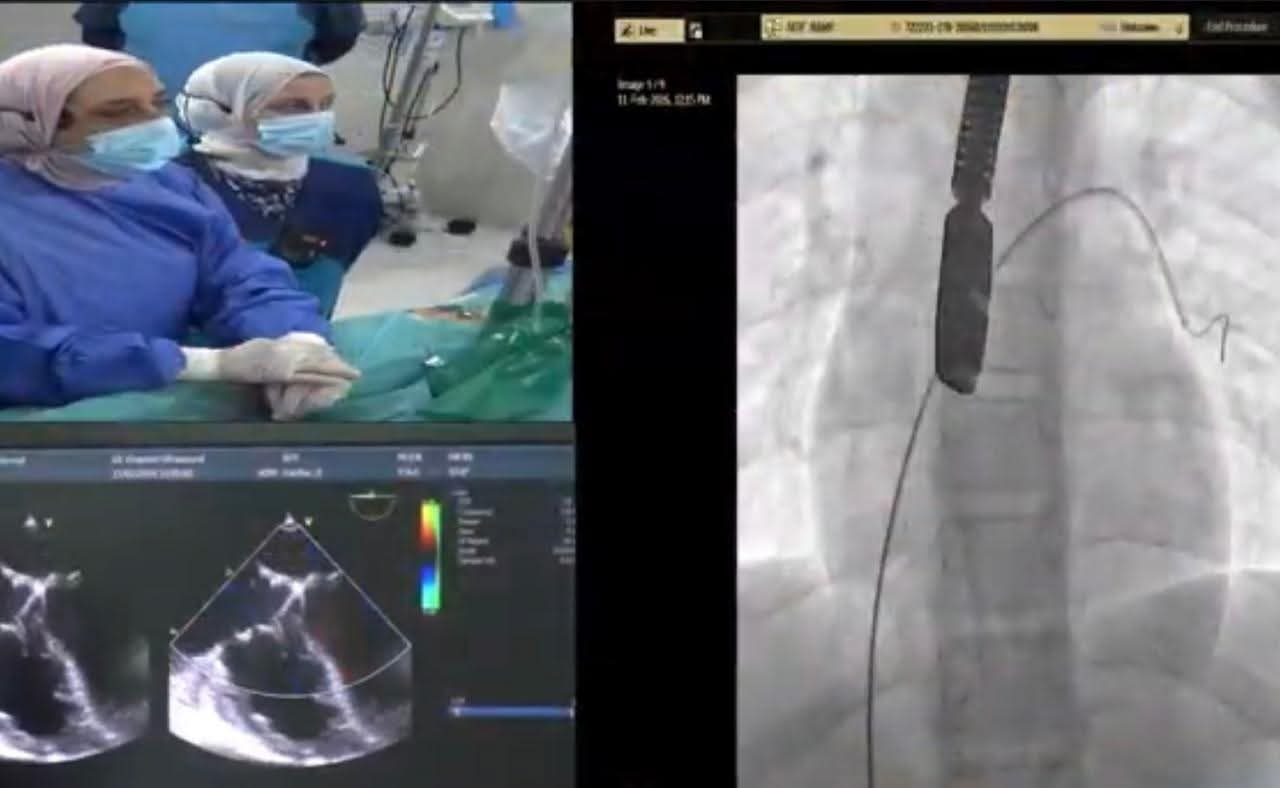

شملت الحالة الأولى طفلًا يبلغ من العمر خمس سنوات من محافظة كفر الشيخ يعاني من تضخم بعضلة القلب بسبب ثقب بين البطينين وتم غلق الثقب بنجاح باستخدام القسطرة التداخلية أما الحالة الثانية فكانت لشاب يبلغ 16 عامًا من محافظة الغربية يعاني من آثار جلطة سابقة وتم غلق ثقب خلقي بين الأذينين ليخرج الطفلان في حالة مستقرة ونتيجة مثالية.

شارك في العملية فريق طبي متكامل من أساتذة القلب والتخدير والعناية المركزة بالإضافة إلى تمريض المستشفى وفنيي الأشعة مما يعكس مستوى الخبرة والكفاءة التي وصلت إليها مستشفيات جامعة طنطا في التعامل مع أصعب الحالات الطبية للأطفال.